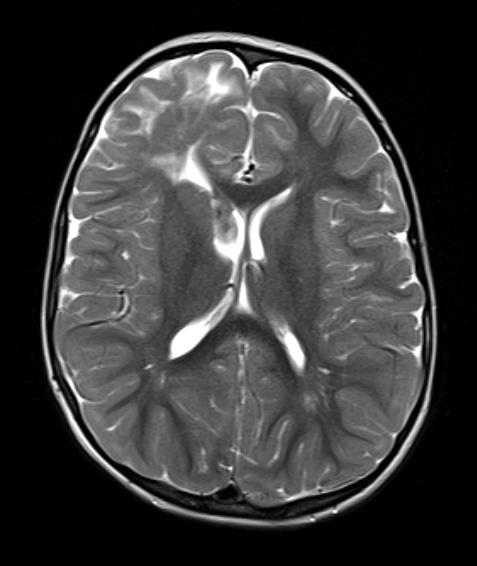

Washington University Experience | DEVELOPMENTAL MALFORMATIONS | Tuberous Sclerosis | 16A5 TS & SEGA (Case 16) T2W A - Copy

The frontal tuber and ventricular SEGA are hyperintense and isointense respectively on T2-weighted scans.